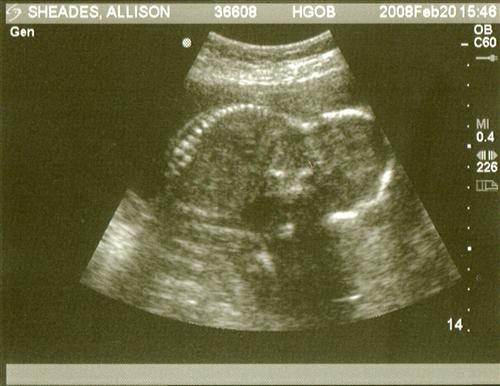

Sono pics... can i see your 20 week ones?

Okay so i went yesterday for my 20 week sono and my pictures S*CK!!!! I don't understand how some of you have such great pictures and mine have been awful!

your sono is cute!!! Your baby is showing us his/her butt!

Awe Ali, he/she is so cute!! Look at that coolie! you can see the spine, so awesome!! you'll get better ones. can you go back and ask for more?

oh its cute... I see the spine!

I guess this picture is better than my 3 month picture! So i can't really complain!

Aaaww I think it's cute how you can see the spine so clearly and how your baby is looking down with his/her little butt up!!!!